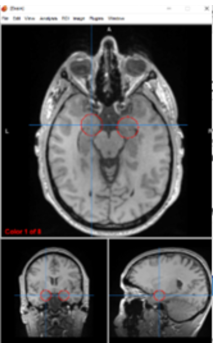

amygdalae

emotional processing, fear conditioning, and memory